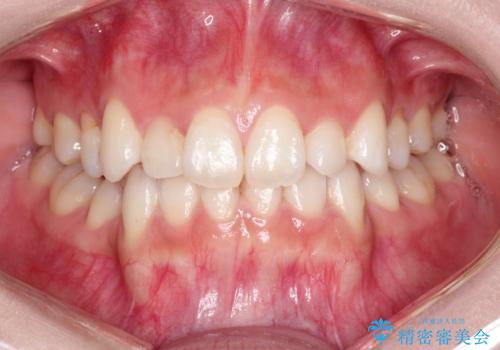

話しにくい歯並びの改善 抜歯矯正治療と前歯の審美治療